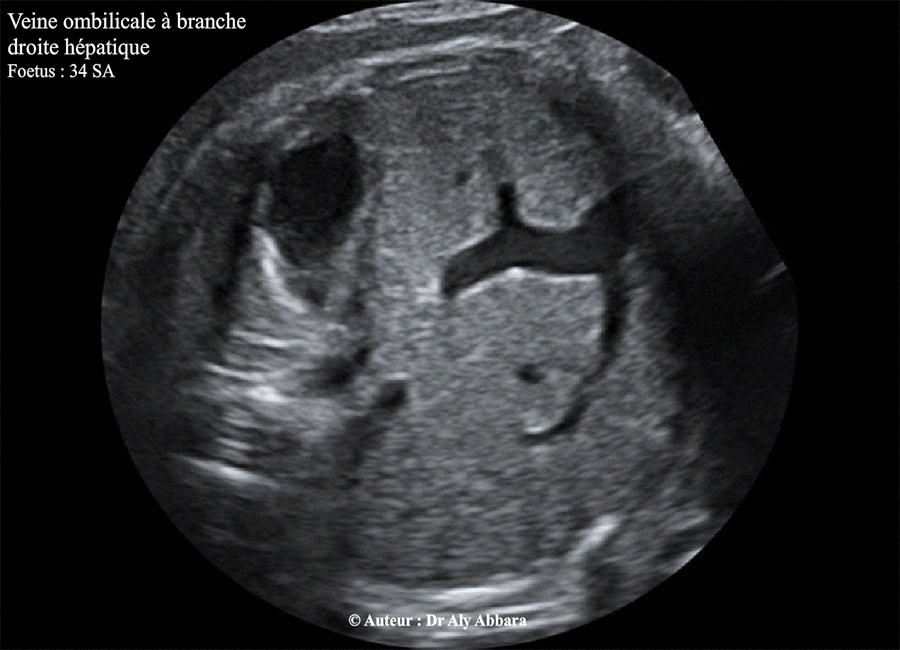

Images échographiques montrant une veine ombilicale gauche à branche droite intrahépatique.

(une variante de la persistance de la veine ombilicale droite ?).

Foetus de 34 SA ; aucune anomalie morphologique associée ; foetus eutrophe à la naissance.

a- Veine ombilicale gauche à branche droite intrahépatique

(le cas présenté dans cette page)